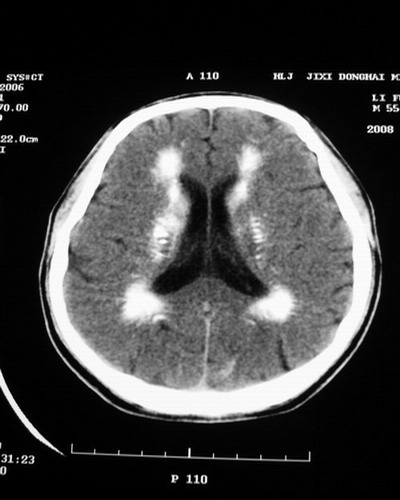

以下是引用随光逐影在2008-1-14 17:26:00的发言:[br]考虑为:甲状旁腺功能低下。需与fahr`s病相鉴别。建议:实验室检查。